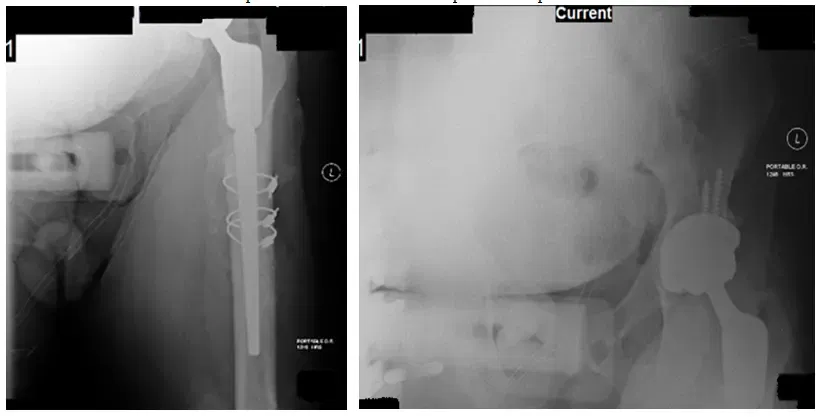

La patiente est une femme de 65 ans qui est arrivée environ 1 an après avoir subi une arthroplastie totale de la hanche droite (THA) et a présenté une fracture du fémur déplacée. Le patient a eu besoin d’une procédure de fixation interne à réduction ouverte (ORIF)...